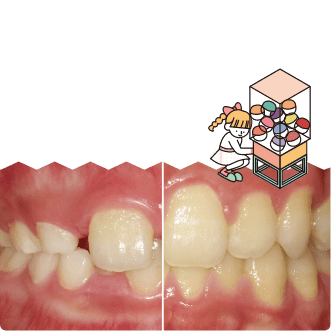

10名を超える歯科衛生士が担当!「年をとると歯が無くなる」なんて思っていませんか?歯を失う原因のほとんどが歯周病です。知らない間に進行する歯周病。まずは検査からはじめましょう!

歯は加齢で失う訳ではなく、むし歯や歯周病が原因です。継続的なクリーニングと正しい自宅ケアを習慣にして大事な歯を残すために、担当制で歯科衛生士がしっかりサポートいたします。